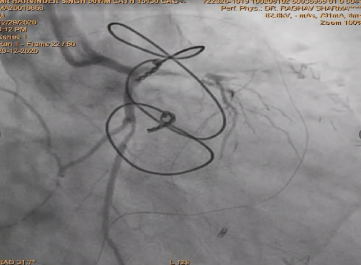

After deployment observed Perforation of SVG-OM Distal LCX post Stenting.

Used two covered stent to cover perforation OM and LCX .

After using covered stent perforation was sealed and TIMI 3 flow achieved